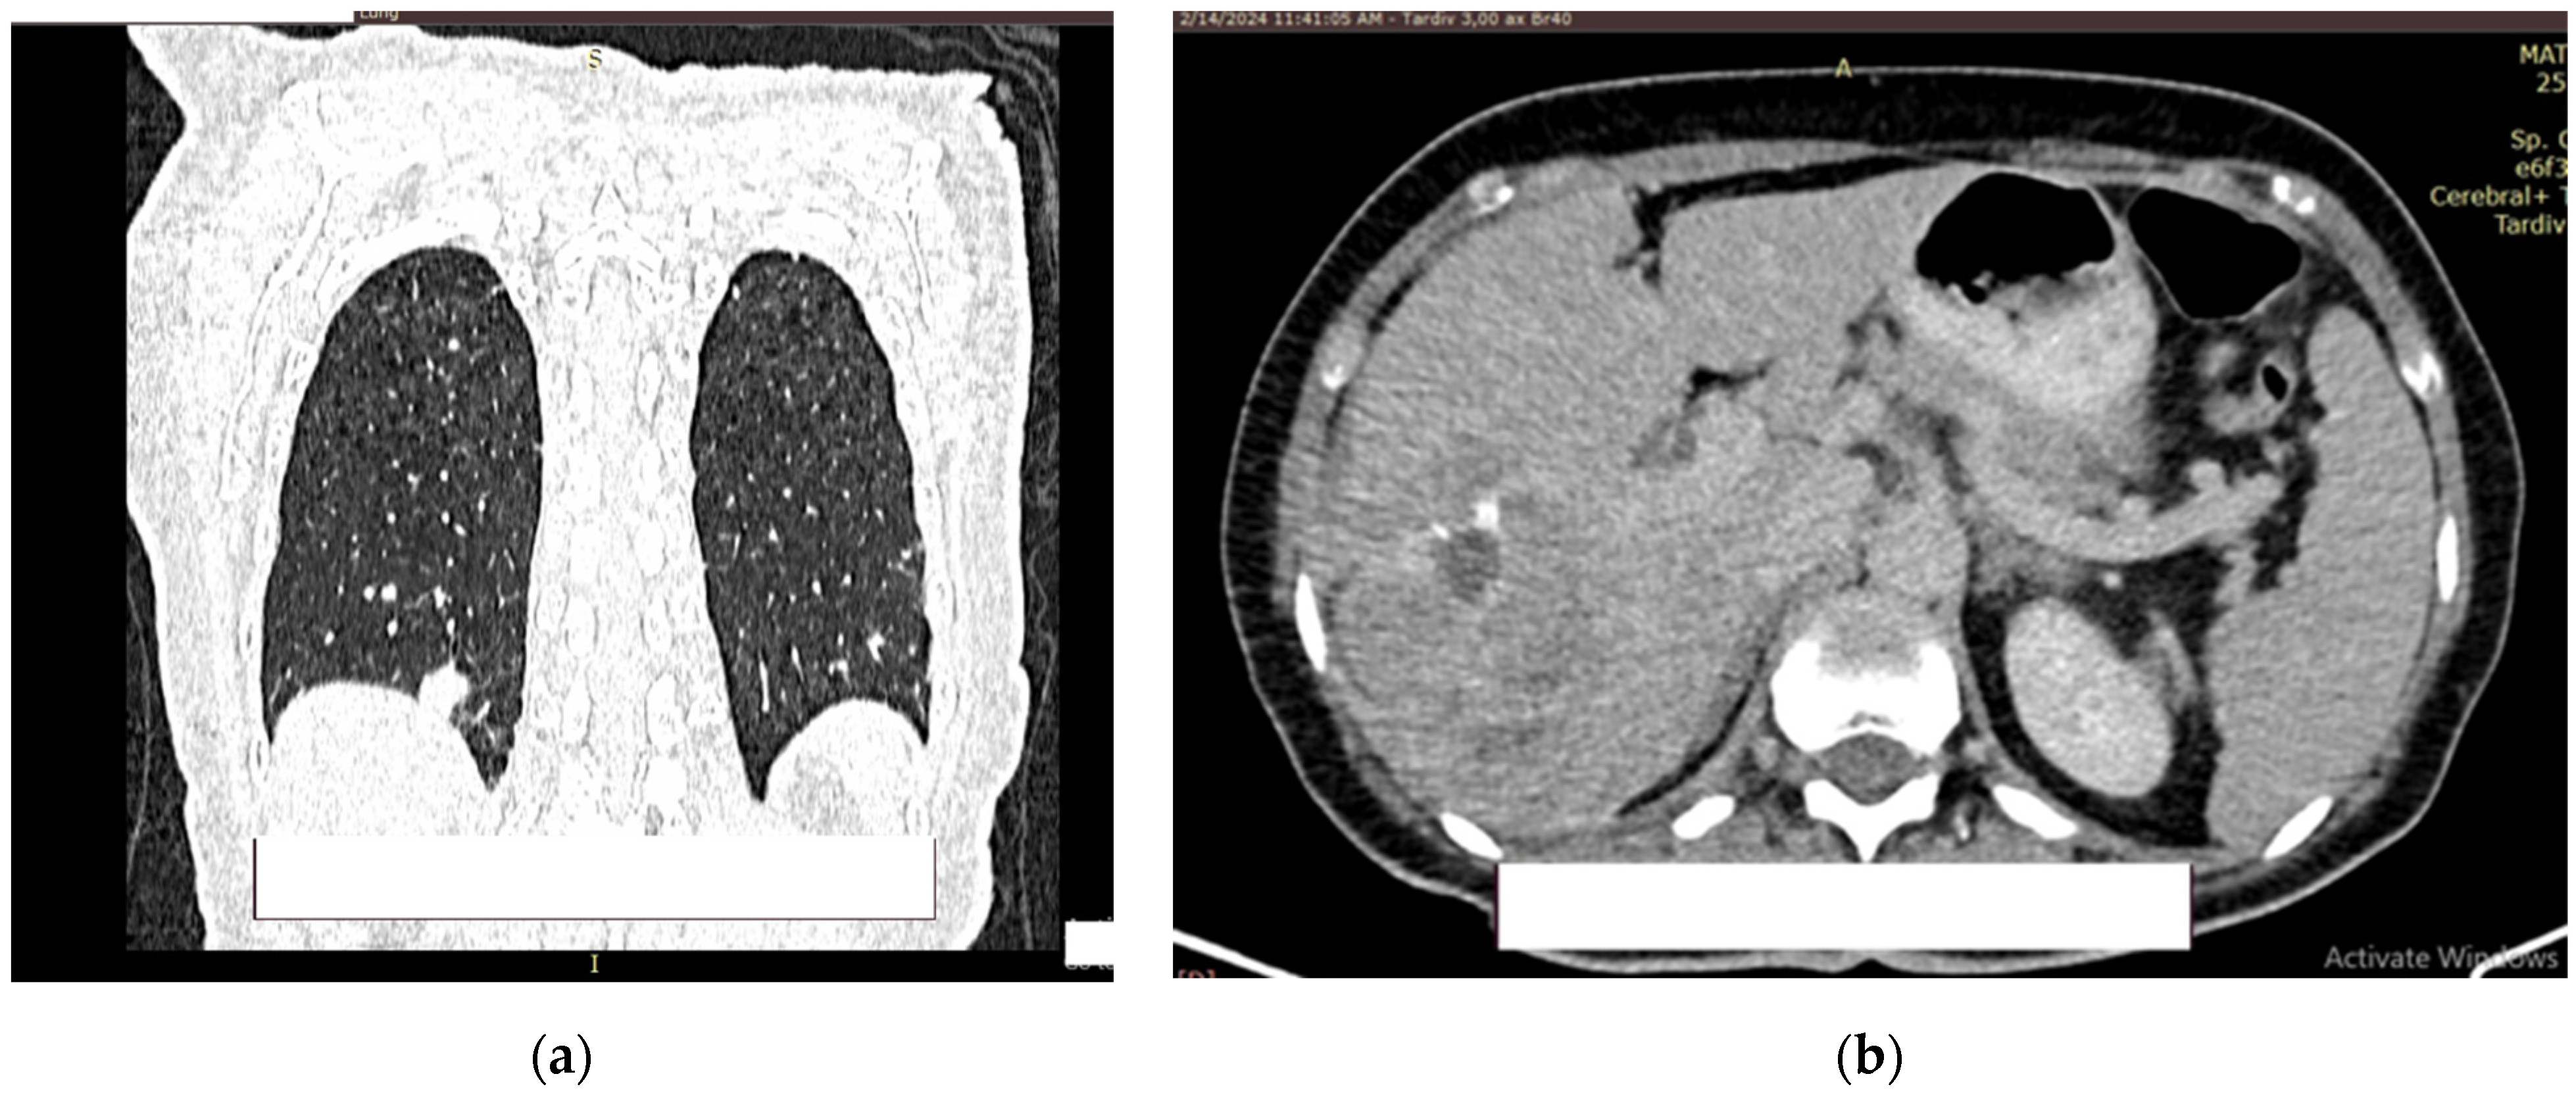

2. Case Presentation